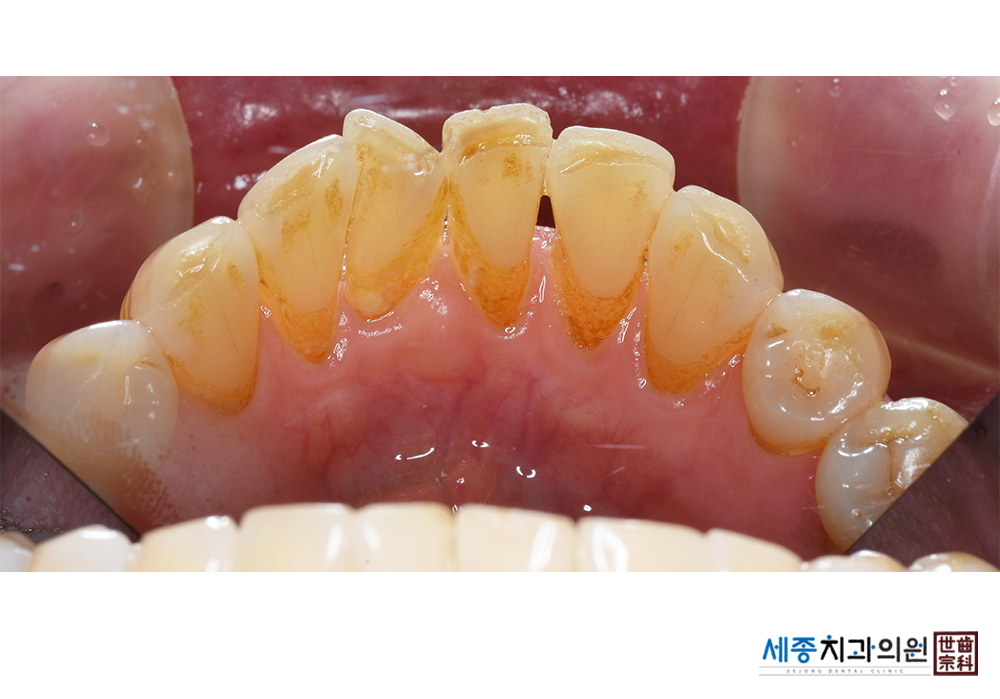

[스케일링] 치주질환 예방 스케일링

치료전 : 2021-01-06

가글마취&저주파 스켈러를 사용한 스케일링